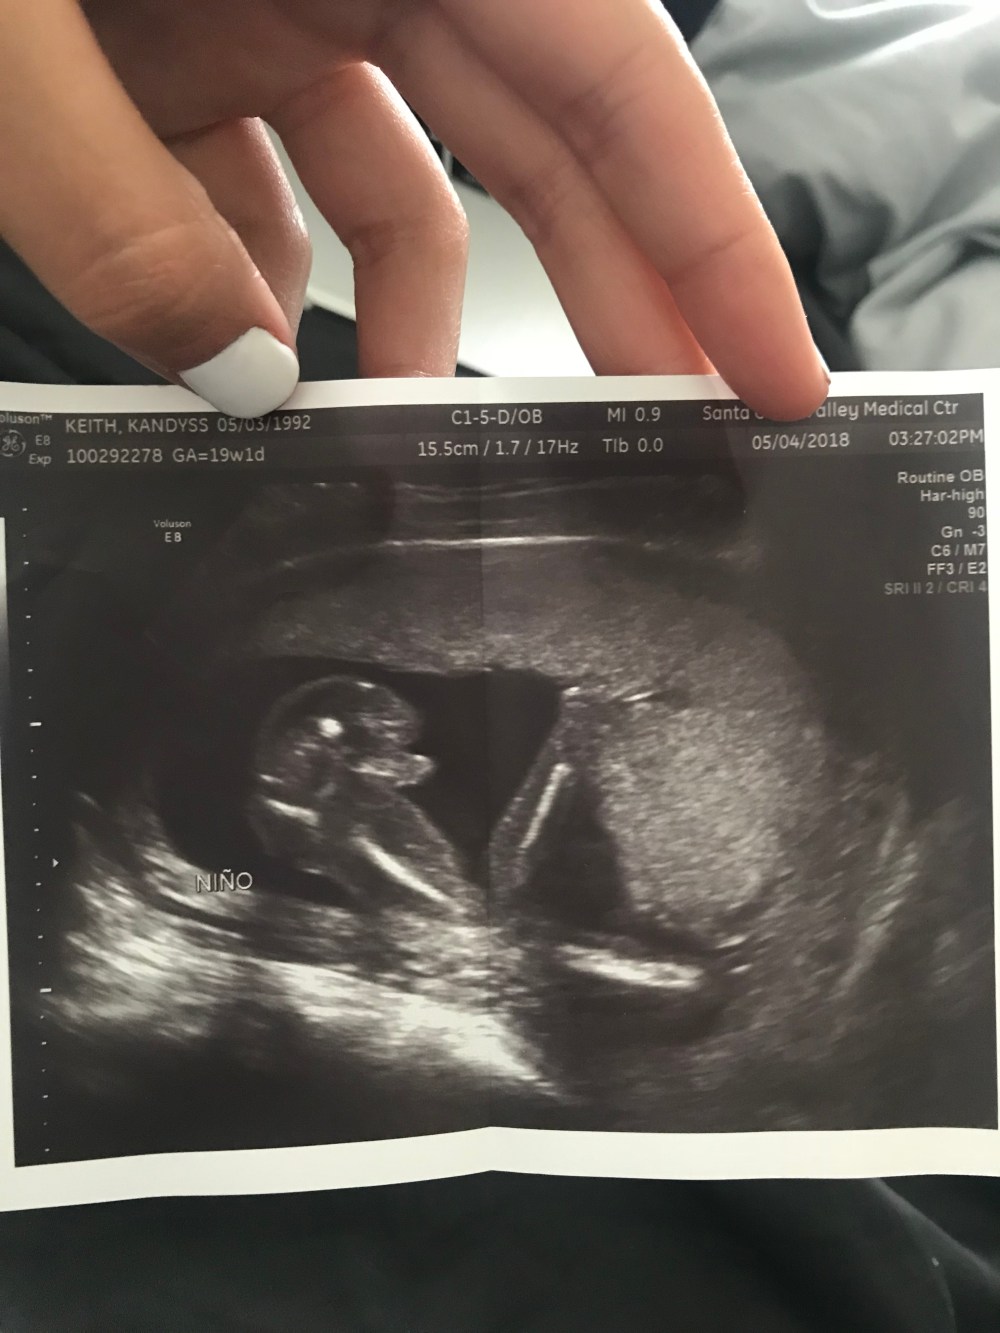

But it took us a good 10 seconds to see in teeny tiny type (that blended in to the background of the sonogram) the word ‘Nino.’ Now I have no idea why the tech put Nino, and not ‘boy’ in big bold letters, but either way, it didn’t matter to me in the moment because I finally got to put a gender to the sweet little bean growing in my belly!